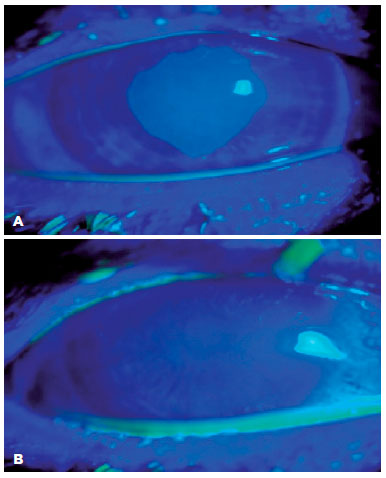

Corneal epithelial healing after CXL was observed after 2.3 ± 1.2 days (range, 1.0-5.0 days) in the TH-SH and 3.8 ± 2.9 days (range, 1-7 days) in the SH group, and the difference was statistically significant (p=0.03). TH-SH patient’s corneal epithelium defect with fluorescein on the first and (A) second postoperative days (B) are shown in figure 1.

Epithelial defects in the central 8.0 mm debridement area of the corneal epithelium were noted in both eyes of 23 patients in the SH and TH-SH groups, respectively, The TH-SH group had epithelial defects with a mean percentage area relative to the whole debrided area of 26.2% ± 31.1% (range, 16%-92%) on day 1, 16.2% ± 21.1% (range, 10%-40%) on day 3, and 8.3% ± 11.1% (range, 0%-10%) on day 5. The SH group had epithelial defects with a mean percentage area of 32.5% ± 25.7% (range, 0.19%-72%) on day 1, 22.8% ± 13.7% (range, 0.15%-58%) on day 3, and 11.5% ± 13.7% (range, 0%-18%) on day 5 with a statistically significant difference between the two groups on day 1 (p=0.021) and day 3 (p=0.047).